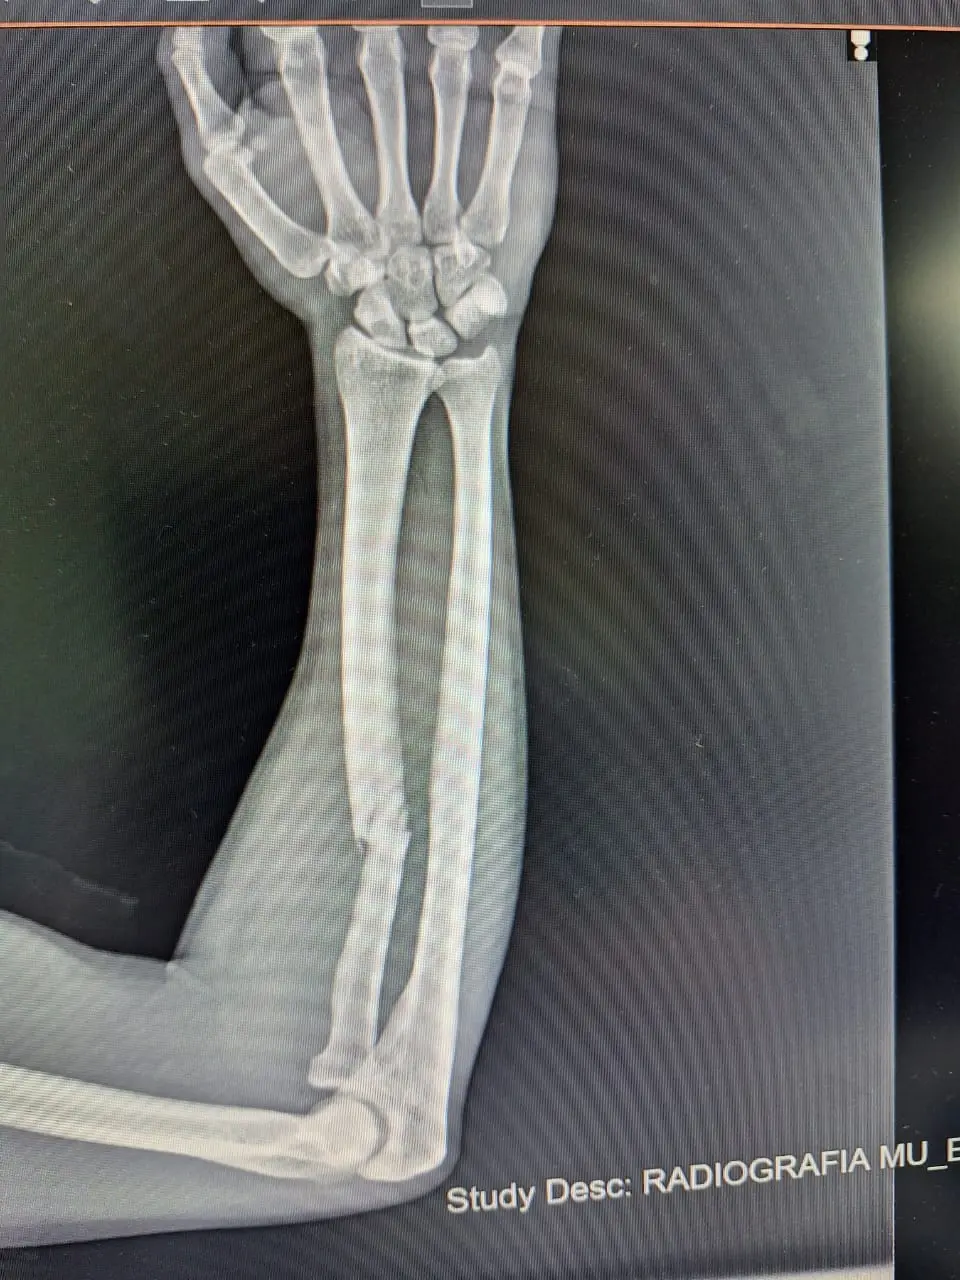

Rodrigo Díaz, de 20 años, sufrió una fractura de radio y necesita una placa de titanio para ser operado.

Como consecuencia del asalto, el joven sufrió una fractura de radio diafisaria en uno de sus brazos. La lesión requiere intervención quirúrgica obligatoria.

Para la operación, Rodrigo debe colocarse una placa recta bloqueada de titanio. El costo del insumo médico asciende exactamente a 1.528.324 pesos.